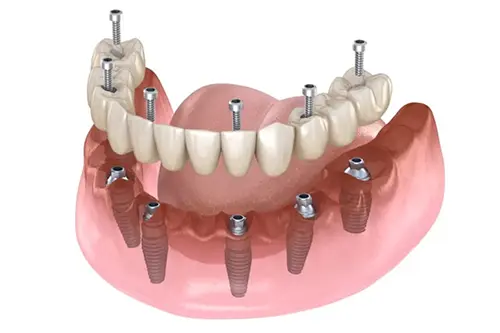

All-on-6 Dental Implants

Ideal for full-arch restorations using fewer implants for maximum stability.

All-on-4 Dental Implants

Like All-on-6 Dental Implants, Perfect for full-arch restorations with fewer implants.